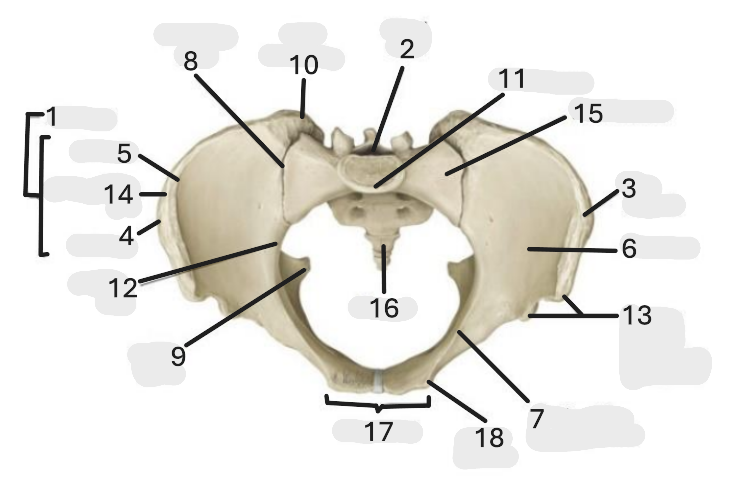

Where is the pelvic inlet

1

Where is the sacro-iliac joint

2

Where is the pubic tubercle

3

Where are the S1 body

4

Where is the ischial spine

5

Where is the ala of sacrum

6

Where is the anterior superior iliac spine

7

Where is the ischiopubic ramus

8

Where is the coccyx

9

Where is the obturator foramen

10

Where is the pubic symphysis

11

Where is the ischial tuberosity

12